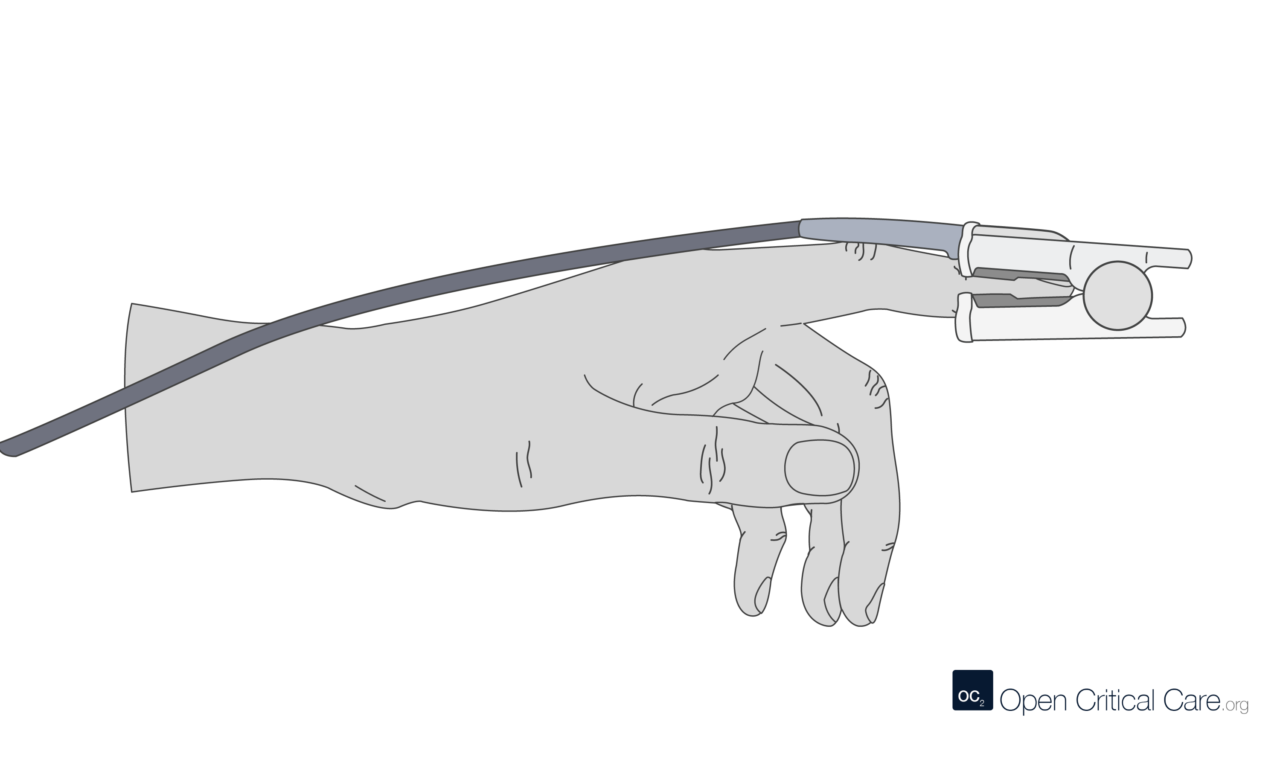

2 – Diagnostic Tools – Spirometry, Arterial Blood gas, Oximeter, Exercise Tolerance Testing, X-ray, Bronchoscopy, Culture and Sensitivity Tests, Sneezing Reflex, Coughing Reflex,

- High flow nasal cannulae – consists of wider – bore prongs and offers humidification and titration of oxygen concentrations to be delivered.